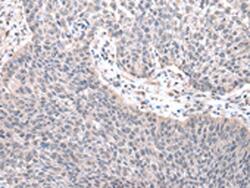

Supportive validation

- Submitted by

- LSBio (provider)

- Enhanced method

- Genetic validation

- Main image

- Experimental details

- Immunohistochemistry of paraffin-embedded Human lung cancer tissue using ZNF239 Polyclonal Antibody at dilution of 1:25(×200)